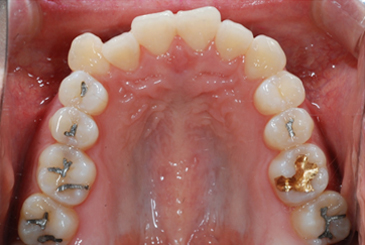

어금니 부위에 미니스크류를 식립하여

고정원을 강화하고 발치공간을 최대한 이용하여

심한 덧니를 치료함